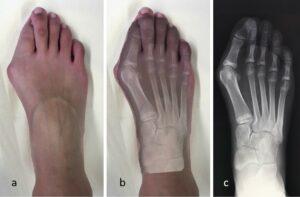

L’Hallux Valgus est la pathologie la plus fréquente de l’avant-pied. Il se caractérise par une déviation du gros orteil (l’hallux) vers l’extérieur, qui s’accompagne d’une proéminence osseuse sur le bord interne du pied : l’exostose, communément appelée « oignon ».

Cette bosse entre en conflit avec la chaussure, créant une inflammation d’une petite poche de liquide (la bourse séreuse) située sous la peau : c’est la bursite, responsable de rougeurs, de chaleur et de vives douleurs.